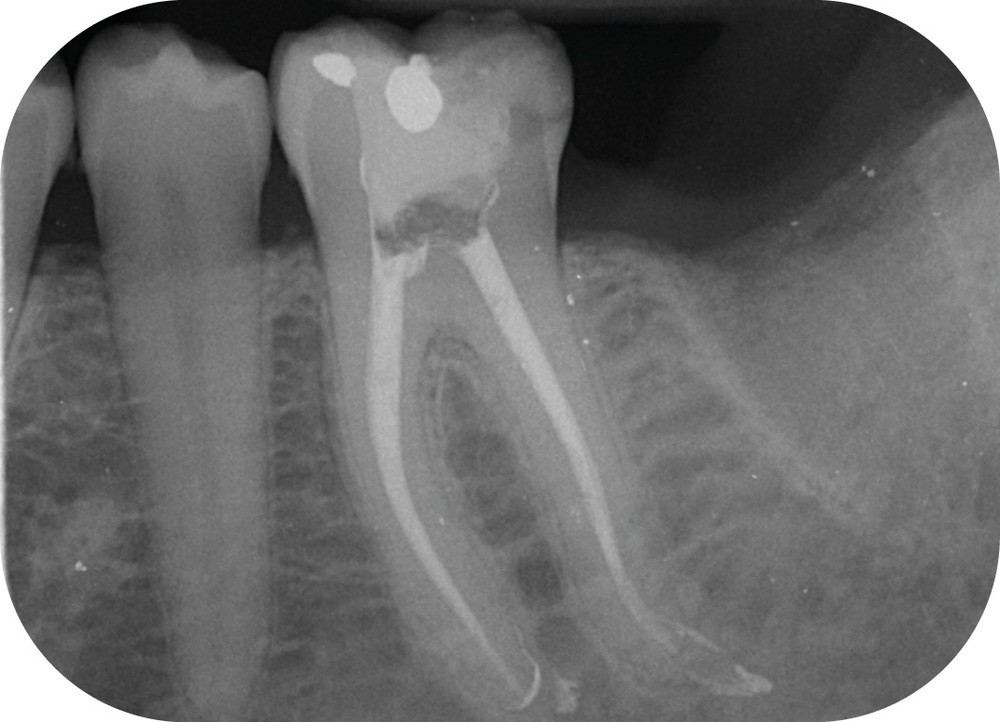

Au moment de la rédaction de ce document, dix-huit systèmes de mise en forme canalaire sont commercialisés sur le marché français. Toutes les publicités promeuvent des améliorations de l’efficacité, de la souplesse et surtout de la résistance à la fracture (fig. 2). Il faut reconnaître que même si ces systèmes sont très différents, les résultats obtenus sont finalement assez constants, et il faudrait des études très poussées pour démontrer la supériorité de l’un par rapport à l’autre (si tant est qu’il y en ait une !).

Parmi les reproches faits à ces systèmes de préparation canalaire, le risque de fracture est celui qui est le plus avancé. Et quelle frustration pour le praticien lorsqu’elle…